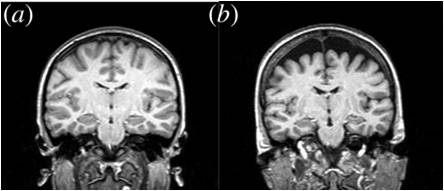

Selective atrophy of left hemisphere and frontal lobe of the brain in old men.

You don't even have to read the paper, though a quick look at the abstract or introduction will confirm that image (b) below shows massive loss of neural tissue from the most recent and advanced areas of the perceptual equipment you are using right now to assess this data.